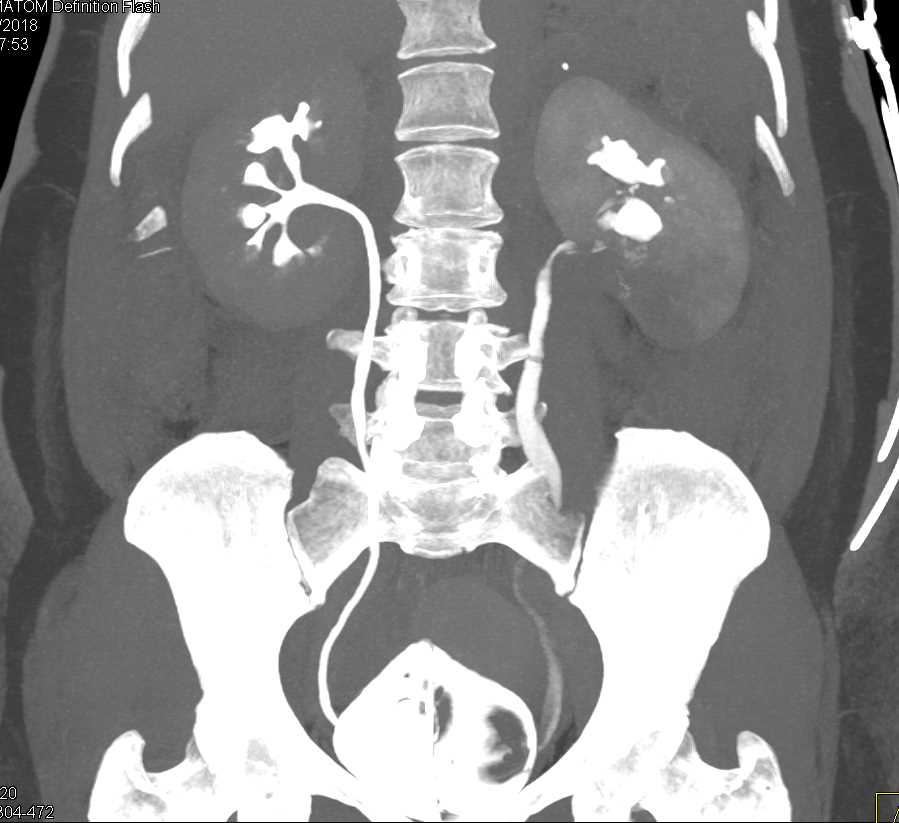

Acute Pyelonephritis Right Kidney